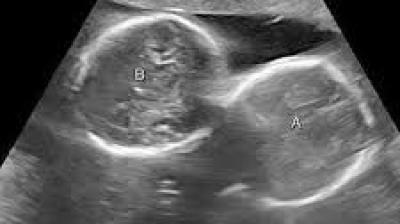

डॉक्टरों के लिए यह मामला हैरान करने वाला रहा

31 Mar, 2026 04:02 PM IST | HAMARASWARAJ.IN

इंदौर। इंदौर के ESIC अस्पताल से प्रेगनेंसी का एक बेहद चौंकाने वाला मामला सामने आया है. यहां पर एक महिला ने तीन बच्चों को जन्म दिया. इससे भी ज्यादा हैरान...